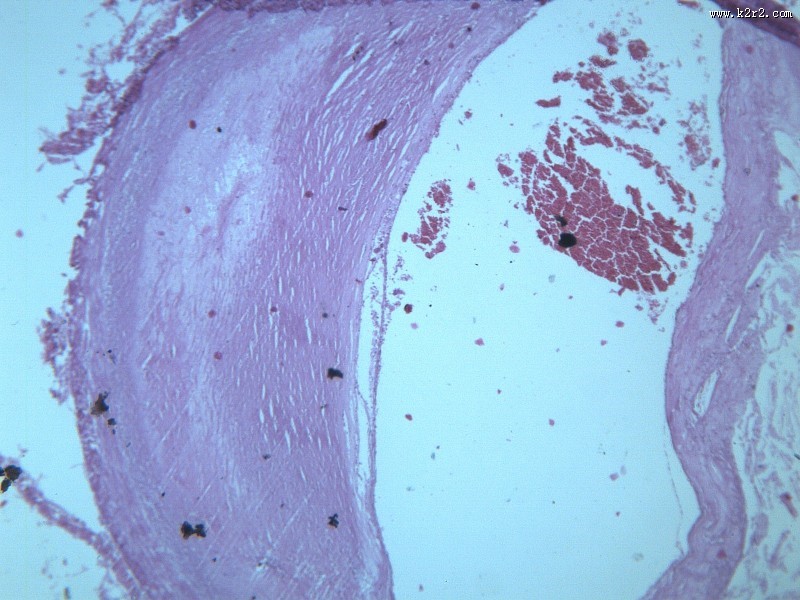

首页 > 其他类别 > 动脉粥样硬化(12张) > 动脉粥样硬化 第1张

动脉粥样硬化 - 第1张

猫扑风铃上传动脉粥样硬化 图集中 / 共有 12 张图片